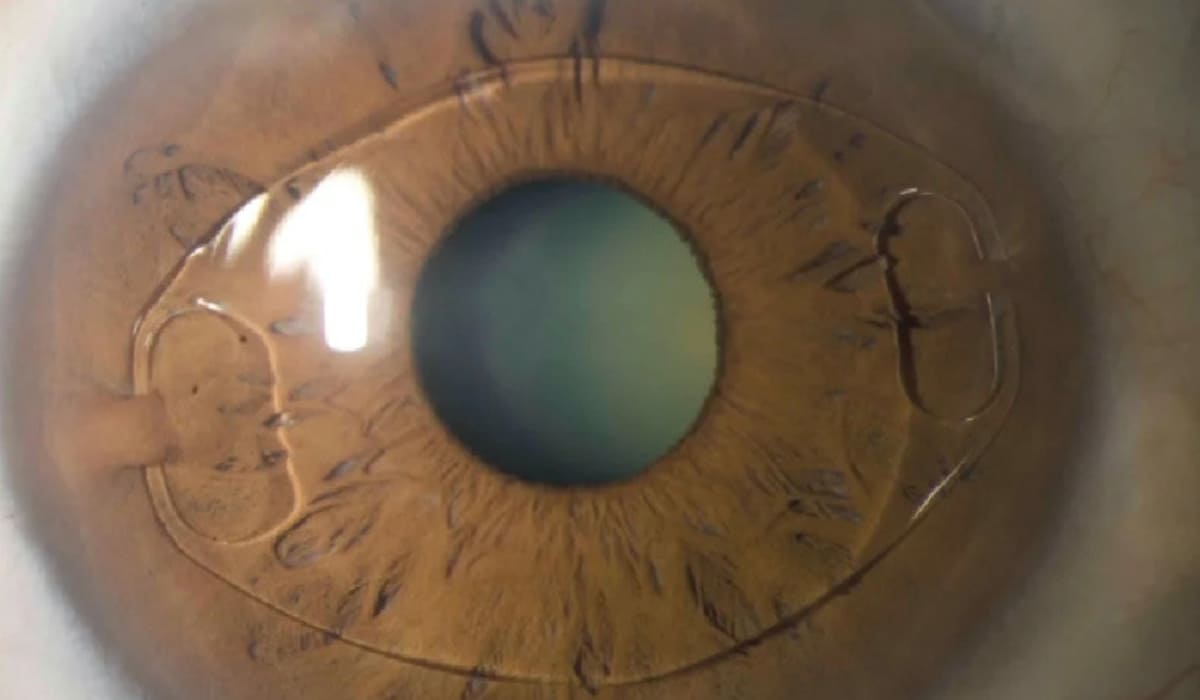

Mổ mắt Phakic là phương pháp hiện đại trong điều trị tật khúc xạ nặng, dựa trên nguyên lý cấy ghép một thấu kính nội nhãn (Intraocular Lens – IOL) đặc biệt vào sâu mống trong mắt. Thấu kính này được đặt ở khoang sau mống mắt và phía trước thủy tinh thể, giúp điều chỉnh chính xác các tật khúc xạ như cận thị, viễn thị và loạn thị mức độ cao. Điểm nổi bật của phương pháp này là không can thiệp bào mòn giác mạc, nhờ đó duy trì nguyên vẹn cấu trúc tự nhiên của mắt.

Các thấu kính dùng trong phẫu thuật Phakic có chất liệu mềm dẻo, linh hoạt và có độ tương thích sinh học cao, an toàn với cơ thể. Thấu kính được thiết kế riêng biệt dựa trên thông số mắt của từng bệnh nhân, nhờ vậy khi cấy ghép vào sẽ mang lại cảm giác thoải mái, không cộm vướng và chất lượng thị giác rõ nét. Đây là lựa chọn điều trị hiệu quả nhất dành cho người bị tật khúc xạ mức độ cao mà các phương pháp khác không thể đáp ứng.

- Bước 3 – Cấy thấu kính IPCL: Thấu kính được gấp gọn và đưa qua đường rạch bằng bộ dụng cụ chuyên biệt. Trong quá trình này, bác sĩ bơm thêm dung dịch nhầy (Viscoelastic) nhằm bảo vệ các cấu trúc trong mắt và tạo không gian thao tác thuận lợi.

- Bước 4 – Định vị thấu kinh và kết thúc: Thấu kính được điều chỉnh chính xác để nằm sau mống mắt và trước thủy tinh thể. Sau đó, lớp gel bảo vệ sẽ được hút rửa sạch. Đường mổ có khả năng tự liền, không cần khâu. Cuối cùng, bệnh nhân được nhỏ thuốc kháng sinh phòng ngừa nhiễm trùng và đeo kính bảo hộ trong giai đoạn đầu hồi phục.